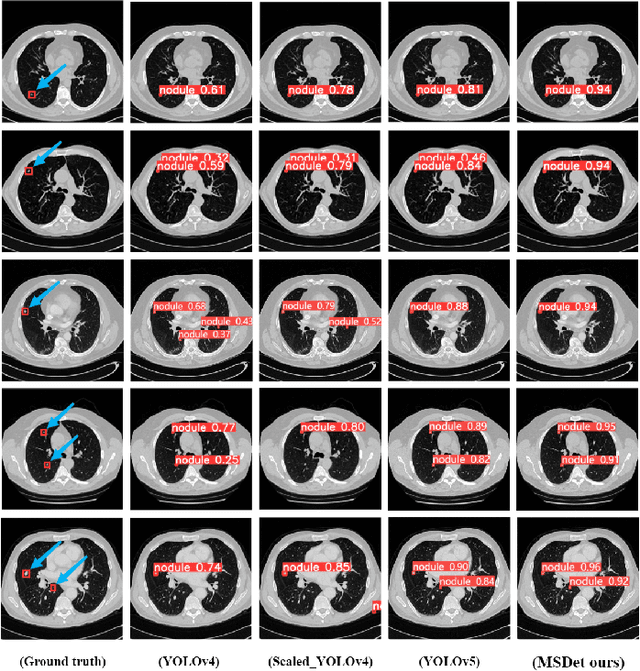

Abstract:Pulmonary nodules are critical indicators for the early diagnosis of lung cancer, making their detection essential for timely treatment. However, traditional CT imaging methods suffered from cumbersome procedures, low detection rates, and poor localization accuracy. The subtle differences between pulmonary nodules and surrounding tissues in complex lung CT images, combined with repeated downsampling in feature extraction networks, often lead to missed or false detections of small nodules. Existing methods such as FPN, with its fixed feature fusion and limited receptive field, struggle to effectively overcome these issues. To address these challenges, our paper proposed three key contributions: Firstly, we proposed MSDet, a multiscale attention and receptive field network for detecting tiny pulmonary nodules. Secondly, we proposed the extended receptive domain (ERD) strategy to capture richer contextual information and reduce false positives caused by nodule occlusion. We also proposed the position channel attention mechanism (PCAM) to optimize feature learning and reduce multiscale detection errors, and designed the tiny object detection block (TODB) to enhance the detection of tiny nodules. Lastly, we conducted thorough experiments on the public LUNA16 dataset, achieving state-of-the-art performance, with an mAP improvement of 8.8% over the previous state-of-the-art method YOLOv8. These advancements significantly boosted detection accuracy and reliability, providing a more effective solution for early lung cancer diagnosis. The code will be available at https://github.com/CaiGuoHui123/MSDet